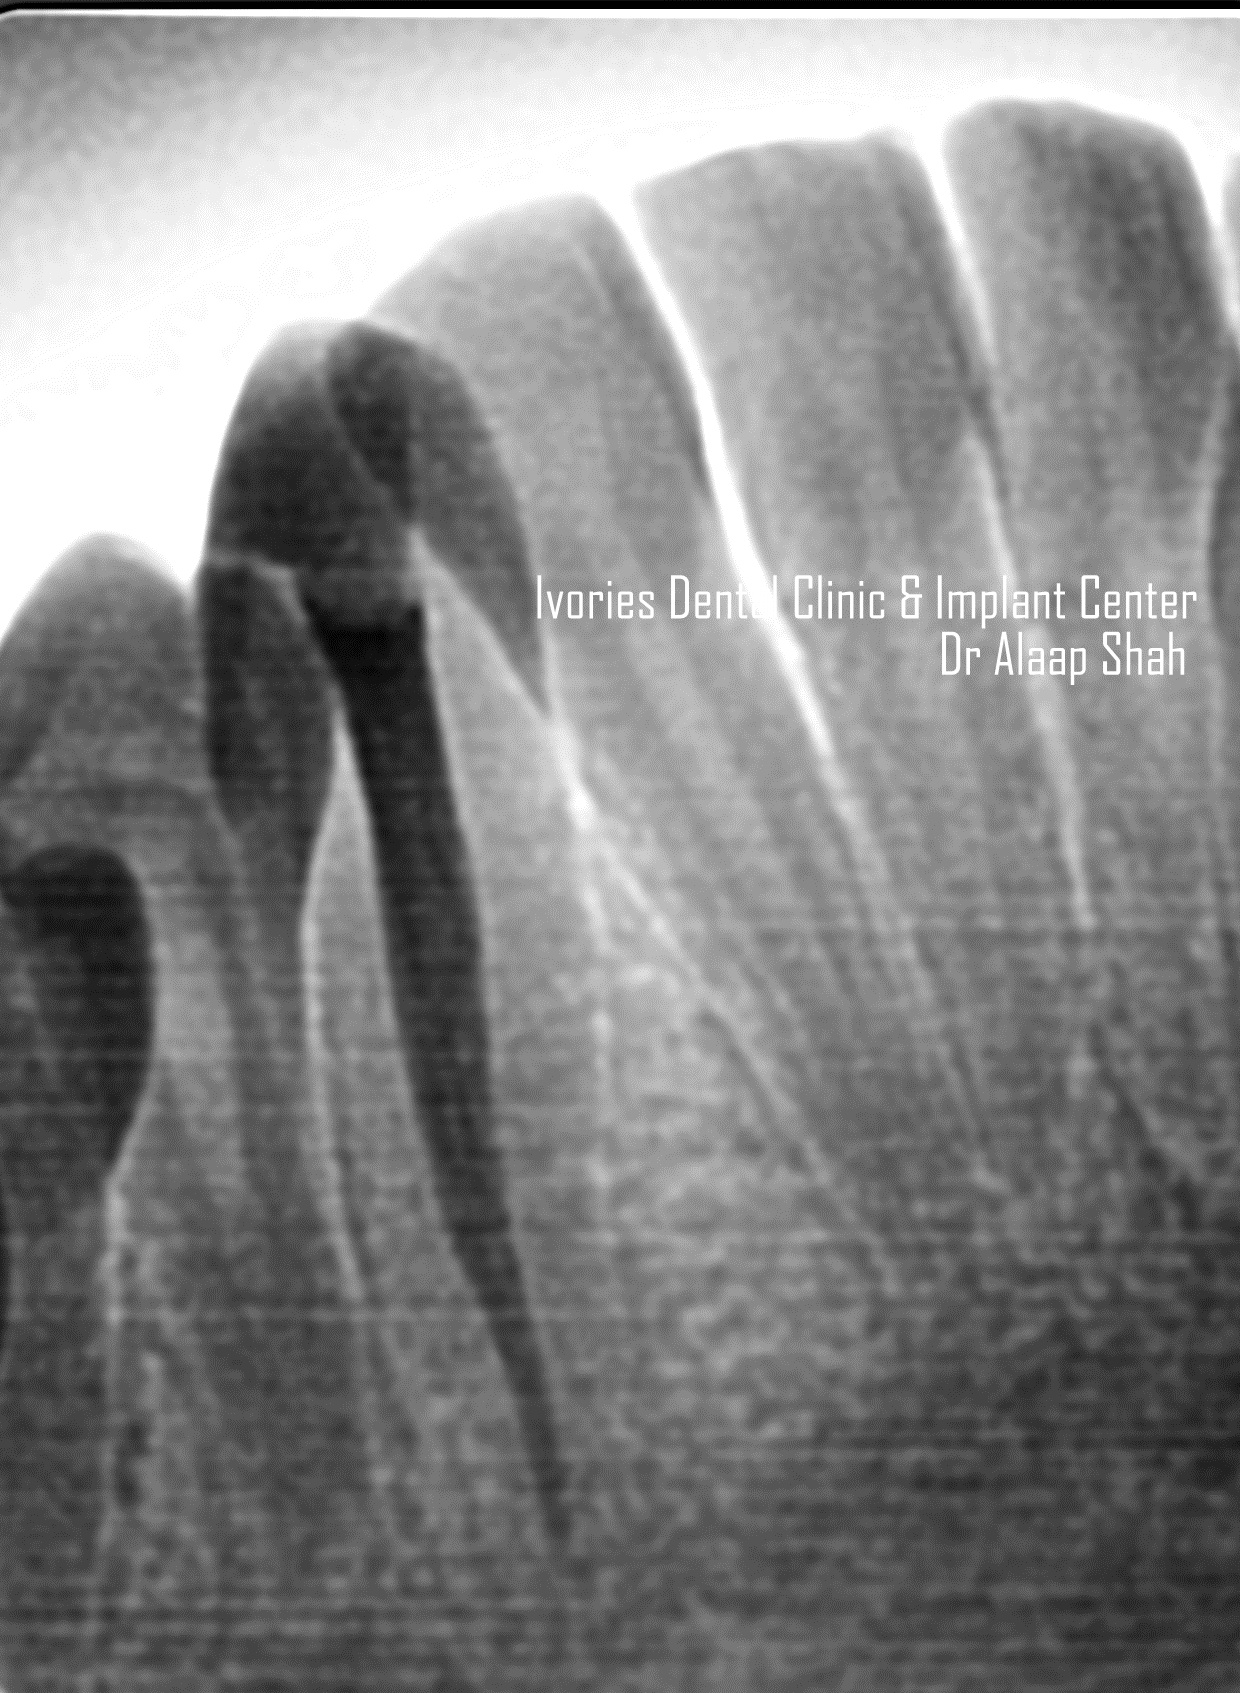

- 3D overview of anatomy of pulp canals

- Tips & tricks to locate the canals & avoid perforations!

- Surgical & Non-surgical treatment protocols for Periapical cyst / radiolucency